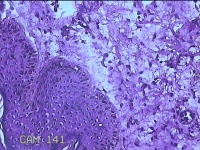

左侧会阴部结节

性别

女

年龄

43岁

临床诊断

皮肤良性肿瘤

一般病史

发现右侧会阴部结节3年余。

标本名称

大体所见

灰白粉红色带皮肤结节0.8x0.7x0.3cm一个,表面光滑,切开结节呈实性,切面灰白粉红色,质韧。